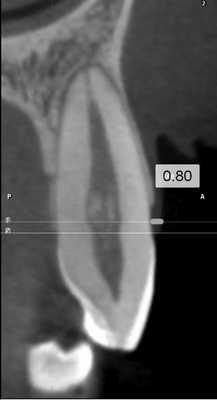

Рис. 5. Измерение расстояния от ЭЦГ до альвеолярного гребня в области зуба 2.3 (без рецессии). В данном случае показатели на 3 реформатах составили: 2,72; 3,04; 3,20 мм.

Для повышения точности исследования проводили 3 вестибуло-оральных реформата относительно центральной оси с шагом 0,5 мм.

КЛКТ проводили на конусно-лучевом компьютерном томографе J. Morita Accuitomo 170, поле сканирования (FOV — field of view) — 8×8 см, угол ротации — 360, размер воксела (Voxel) — 0,16 мм.

Перед оценкой данных проводили настройку коррекции яркости и контрастности для максимальной визуализации вестибулярной костной пластинки, а также центрирование осей координат по вертикальной оси зуба для стандартизации прохождения среза.